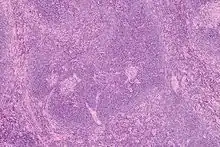

Intermediate magnification micrograph of Castleman disease showing the characteristic expansion of the mantle zone. H&E stain.

Mantle zone expansion may be seen in benign, such as Castleman disease, and malignancy, i.e., Mantle cell lymphoma. Tcl-1 is expressed in the mantle zone.